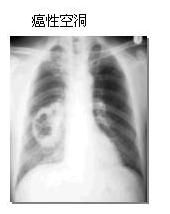

氯甲醚肺癌空洞1原發性肺癌診斷明確。

(一)X線檢查X線檢查是診斷肺癌最常用的重要手段。通過X線檢查可以了解肺癌的部位和大小。早期肺癌病例X線檢查雖尚未能顯現腫塊,但可能看到由於支氣管阻塞引起的局部肺氣腫、肺不張或病灶鄰近部位的浸潤性病變或肺部炎變。中央型肺癌常顯示肺葉或一側全肺不張,靠近肺門區邊緣不整齊或分葉狀腫塊和縱隔淋巴結腫大影像。癌腫病灶中心部分壞死形成空洞者則顯示腫塊內有偏心性透亮區,空洞壁厚,內壁凹凸不平,較少呈現液平面。周圍型肺癌最常見的X線表現為肺野邊緣部位孤立性圓形成橢圓形塊影,直徑從1~2cm~5~6cm或更大。塊影輪廓不規則,常呈現小的分葉或切跡,邊緣模糊、毛糙,常發出細短的毛刺影。病變進展後腫塊周圍尚可出現肺不張、肺炎、胸膜腔積液等徵象。高電壓攝片有助於判明病變性質。靠近肺門區的癌腫大多為鱗狀上皮細胞癌和未分化小細胞癌,前者常伴有阻塞性肺炎、肺不張或肺實變,以及肺門或/和縱隔淋巴結腫大。大多數腺癌和大細胞癌以及一部分鱗狀上皮細胞癌和小細胞癌位於肺野邊緣部位,肺尖部癌腫大多為鱗狀上皮癌。腫塊直徑大於4cm者常為鱗狀上皮細胞癌,且較常形成癌性空洞。細支氣管肺泡癌的X線表現大多為周圍型孤立性結節狀病灶,範圍較為廣泛的結節狀浸潤,類似支氣管或大葉性肺炎,有時呈現空洞。